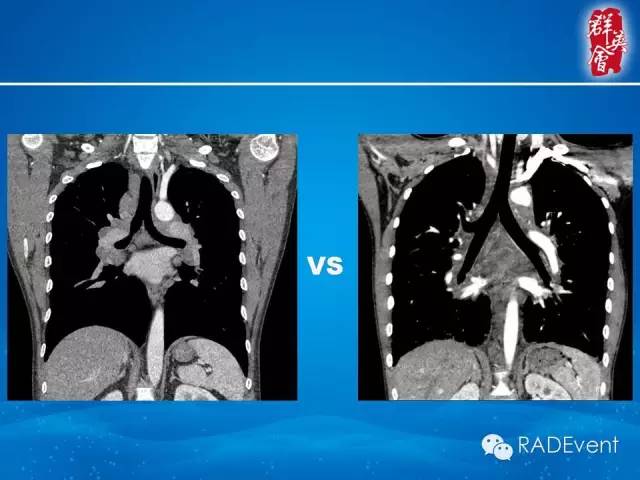

【病例】弥漫性肺淋巴管瘤病1例CT影像表现